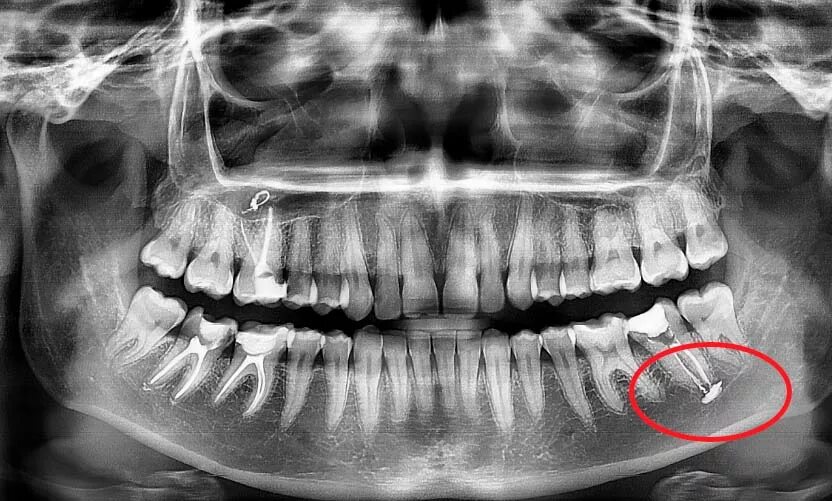

Снимок верхней и нижней челюсти